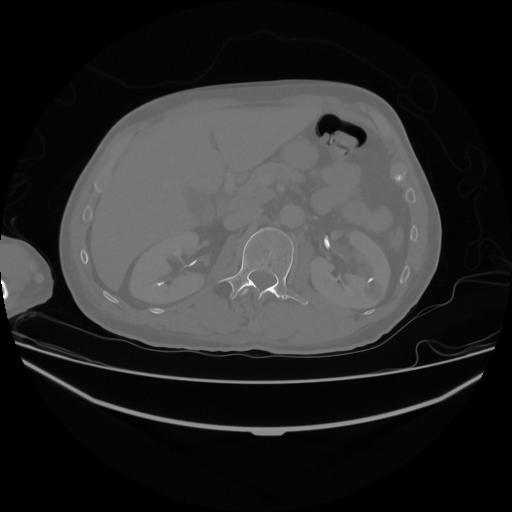

5 CUERPO,CE,Vol,1.0,CUERPO,,